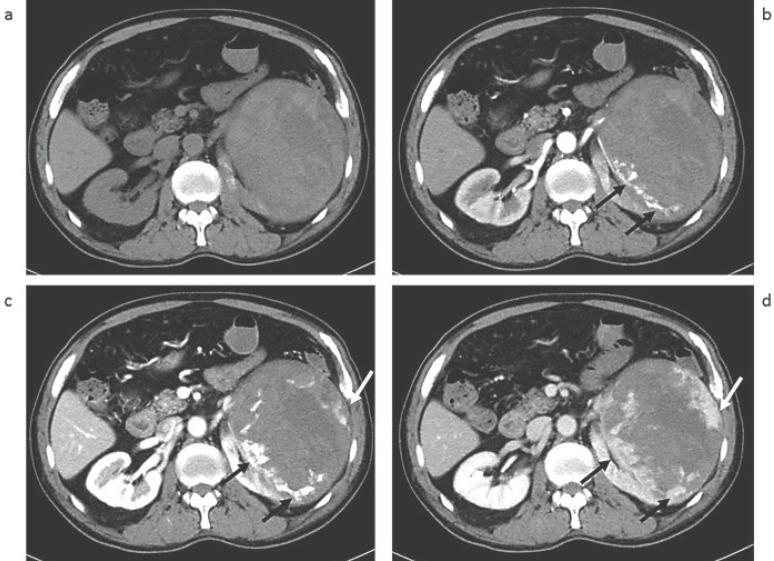

Primary angiosarcomas of the kidney are very rare but highly aggressive tumors showing poor prognosis. We present a case of primary renal angiosarcoma occurring in a 60-year-old man with left flank pain. CT images depicted a huge exophytic mass (14 cm in diameter) in the left kidney, exhibiting central extensive hemorrhage or necrosis without contrast enhancement. The mass showed centripetal peripheral nodular enhancement on dynamic contrast-enhanced CT images. We suggest its inclusion in the differential diagnosis of cases of hemorrhagic renal tumors with prominent vasculature.

原发性肾血管肉瘤非常罕见,但具有高度侵袭性,预后较差。我们报告一例发生在一名60岁男性身上的原发性肾血管肉瘤,该患者有左侧腰痛症状。CT图像显示左肾有一个巨大的外生性肿块(直径14厘米),中央有广泛出血或坏死,无对比增强。在动态对比增强CT图像上,该肿块呈向心性外周结节状强化。我们建议将其纳入对具有显著血管系统的出血性肾肿瘤病例的鉴别诊断中。